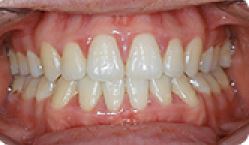

치아교정 세라믹브라켓-1 | 2020.03.19 |